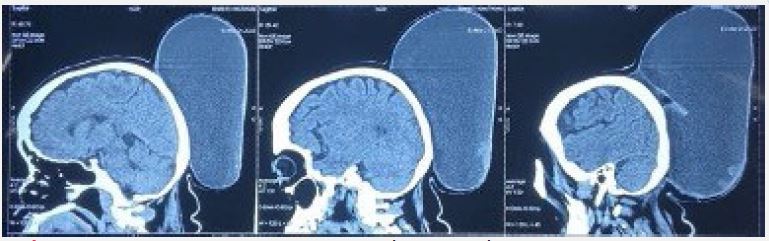

The patient was diagnosed with a large epidermoid cyst based on the findings. Lipoma and dermoid cyst were also considered as potential differential diagnoses. A preoperative Non-Contrast-CT scan of the skull was done to check for any bony or intracranial involvement. The scan revealed a large multiloculated, thin-walled, cystic fluid collection measuring 26×24×12 cm. The cyst was found in the deep scalp layers of the left parieto-occipital region and extended from the midline posterior high parietal region up to the posterior aspect of the occipital bone, abutting their outer cortices, with normal underlying bone with no intracranial extension of the lesion.

Figure 2: Preoperative NCCT Head-Saggital cuts.